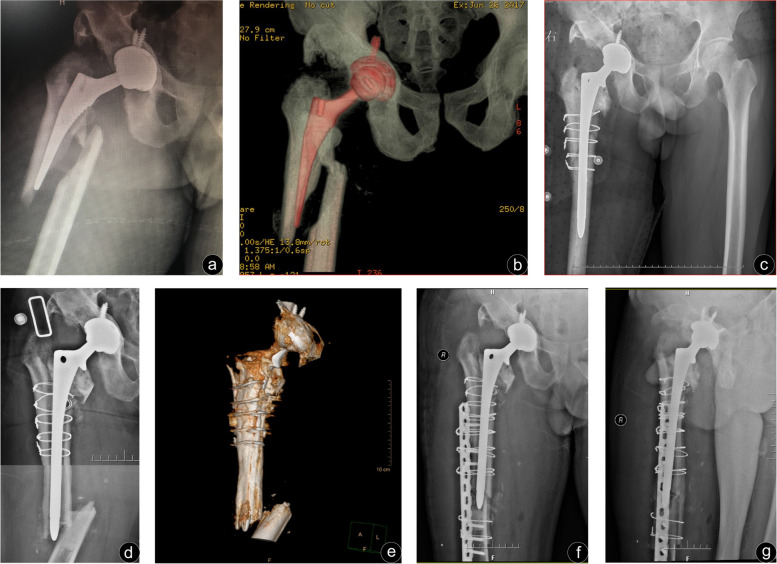

Fig. 3.

A 53-year-old male who sustained a periprosthetic femur fracture 2 years after primary total hip arthroplasty. Three years after revision, there was another periprosthetic fracture. a, b Preoperative anteroposterior X-ray and three-dimensional reconstruction of the femur showed a spiral fracture. No signs of prosthesis loosening were observed. c The femoral stem was loosened intraoperatively and long-stem revision was used for treatment. d, e The anteroposterior radiographs and three-dimensional reconstruction of the femur showed a short transverse fracture. f, g The anteroposterior radiographs on the 2 weeks after the operation which use locked compression plate Fixation, with allograft strut showed satisfactory fracture reduction and good alignment

In the two groups of postoperative complications, there was a possibility of dislocation taking into account the intraoperative dislocation of the hip joint. No dislocation patients occurred in either group. One patient experienced incision infection after operation. One patient in Group B presented with persistent incision exudation, no fever, local red or other signs of infection. And the clear reddish liquid could be squeezed out during daily dressing change, but the bacterial culture was negative. One week later, incision debridement combined with intravenous antibiotics was performed, and the wound finally healed. One patient in Group B needed to be operated again due to the superficial hematoma in the incision, and the wound healed after drainage and wound compression dressing. Group A patients with nonunion fractures were transverse fractures with medial cortical discontinuity, which were fixed by Wagner SL stem (Zimmer, Warsaw IN, USA) combined with cortical allogeneic. It is worth mentioning that the patient who underwent total hip arthroplasty and subtrochanteric shorting osteotomy due to Crowe type IV Developmental dysplasia of hip (DDH) sustained a Vancouver type B1 fracture (Fig. 2a, Fig. 2b) and a standard ORIF regimen was conducted without cortical strut (Fig. 2c, Fig. 2d). As a result, she suffered from the malunion with 15°malunion at the osteotomy site (Fig. 2e) and had a poor function (HHS score 65), but no further revision was performed as economic condition (Fig. 2). There were no cases with deep vein thrombosis in the two groups during the perioperative period, and no cases with screw breakage or femoral stem loosening in the last follow-up.

The most important finding of this study was that LCP alone could obtain a similar clinical effect for Vancouver type B1 fracture when compared with the combined use of LCP and cortical strut allografting. A string of postoperative evaluation indexes, including the fracture union rate and HHS of patients at the last follow-up, demonstrated no statistically significant differences between the two groups. What calls for special attention is that, contrary to our findings, a previous study reported the addition of strut allograft contributed to a higher union rate [13]. We speculated that fracture union was probably related to the age of patients with fracture. The mean age of participants in Khashan et al. ‘s study was 80.4 years old while the mean age in our study was only 65.4 years old. Studies have shown that advanced age is one of the factors affecting fracture healing [22, 23], which may explain the lower union rate in the fracture group treated with the LCP alone in his study. We tried to draw firm conclusions by reviewing the previous literatures, but this remains an area of controversy. Buttaro et al. [24] treated Vancouver type B1 periprosthetic fractures with LCP alone in 9 hips, and 5 patients were treated using LCP with cortical strut allografts. Over an mean follow-up of 20 months, they reported 6 cases of nonunion, all of which occurred in 9 patients without cortical strut. Khashan et al. [13] made a similar study through retrospectively analyzing 21 cases Vancouver type B1 and C fractures. The union rate in the group treated with LCP alone was only 45.5% (5/11), while that in the group fixed by LCP and cortical strut allografts was as high as 100% (10/10). A system review of type B1 fracture by Moore et al. [25] showed that, however, there was no statistical significance in the fracture union rate between the LCP combined cortical strut group (91.5%) and the LCP group (90.7%). At the same time, the strut allograft is usually used for treat the other fractures. Rollo et al. [26] reported a superior outcome in the management of periprosthetic knee fractures without cases of nonunion using plating associated to cortical strut. Also, it’s favourable for revision in breakage of femoral nails [27]. The cortical strut allograft, which we believe should be effectively used when needed, such as advanced age patient, severe osteoporosis, bone defect, short transverse fracture (Fig. 3d-g) and the discontinuity of medial femoral cortex. In our study, discontinuity of the proximal femoral cortex due to subtrochanteric osteotomy in one patient didn’t get our adequate attention and the consequence is that the proximal unicortical screws fixed LCP was pulled out. We reckoned that the fixation of the proximal unicortical screws combined with cerclage wire did not appear to be stable, and that the fixation of the proximal fracture remained the weakest link in the plate structure due to the presence of the femoral stem. Moreover, gravity played an important role in malunion for some patients who were too optimistic about their condition to weight-bear prematurely. A strategy for type B1 fracture in Corten et al’s study suggested [20], the discontinuity of medial femoral cortex have been used as the indication for cortical strut. Although we have not successfully treated similar cases, the authors suggest that cortical strut fixation appears to be necessary in this condition.